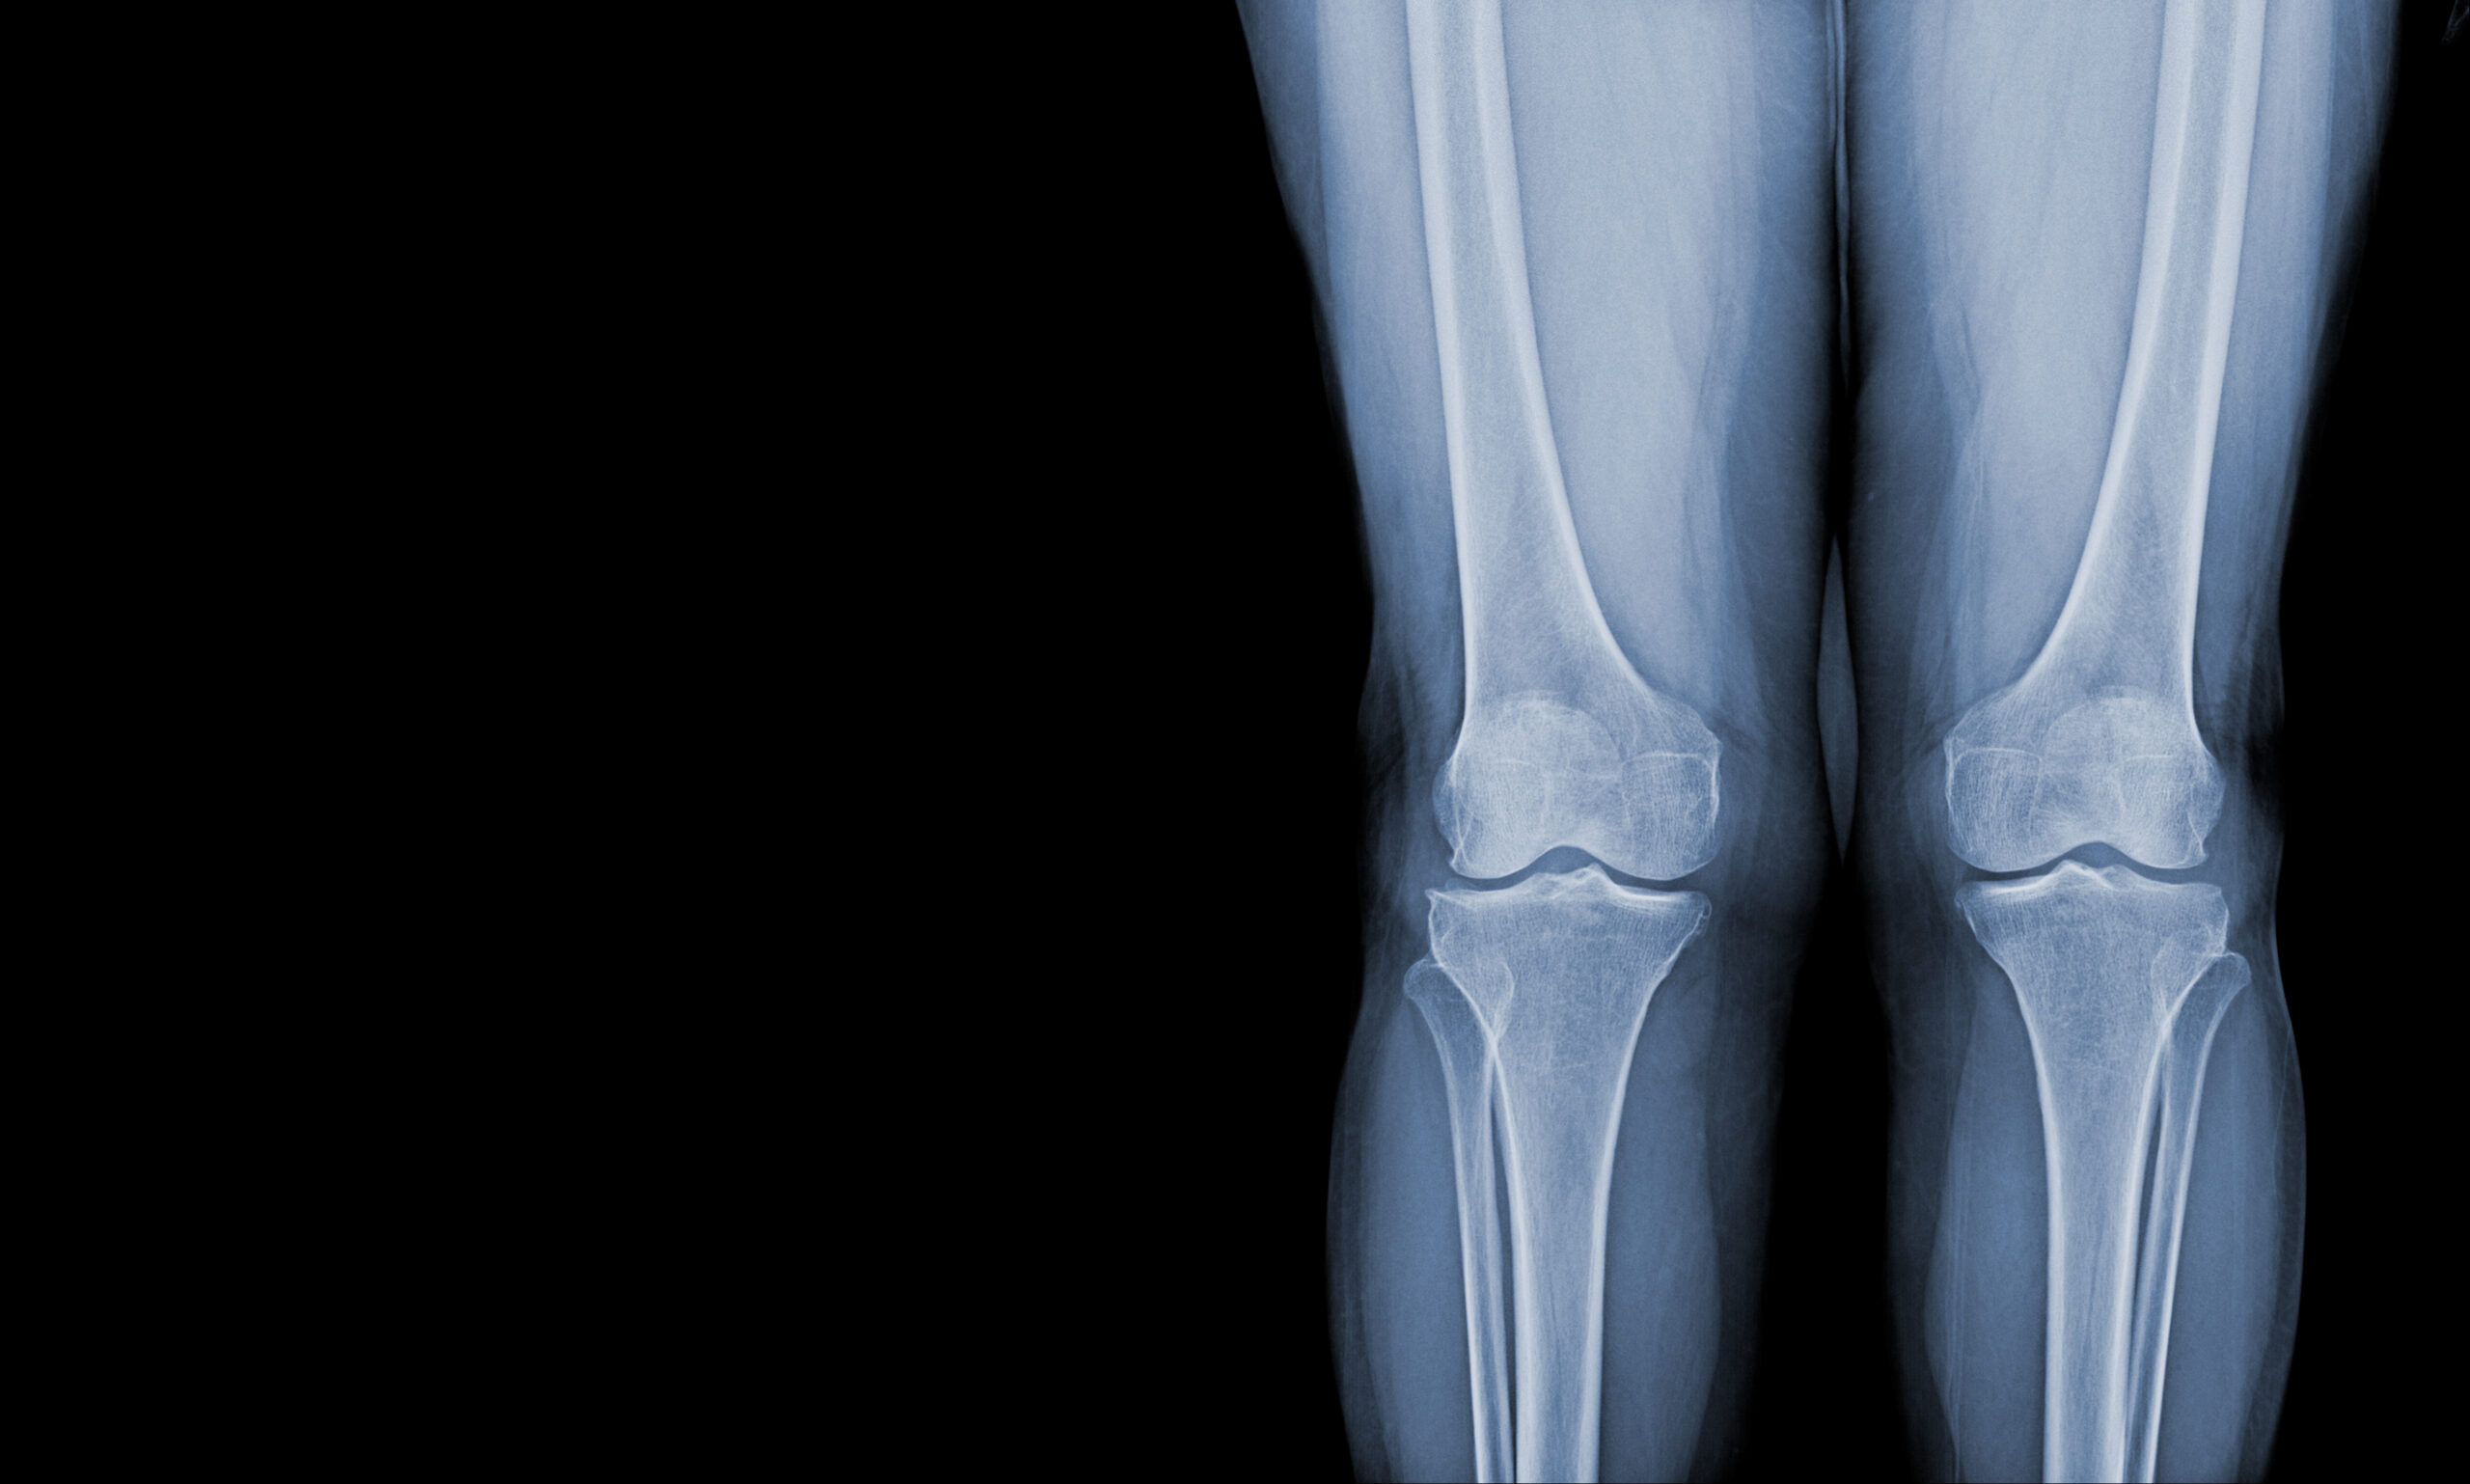

A scanogram is a special type of X-ray. It helps doctors measure the length of bones in your body. Often, doctors use a scanogram to check if your legs are the same length. This scanogram procedure is quick and painless. Because it gives clear images, it helps doctors plan treatments or surgeries. According to the World Health Organization (WHO), X-rays like scanograms are safe when used properly.

A scanogram uses X-ray technology to create images of your bones. First, the machine takes a series of X-rays at different points along your leg or arm. Then, a computer puts these images together. As a result, your doctor can measure the exact length of each bone. Unlike regular X-rays, a scanogram focuses on measurement, not just pictures. This makes it very useful for certain bone problems.